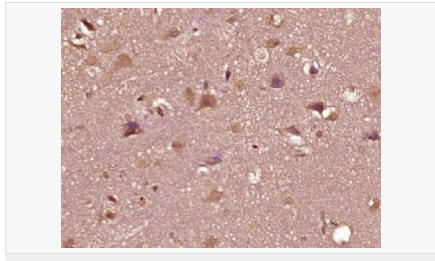

| 产品应用 | WB=1:500-2000 ELISA=1:5000-10000 IHC-P=1:100-500 IHC-F=1:100-500 Flow-Cyt=1ug/Test IF=1:100-500 (石蜡切片需做抗原修复) not yet tested in other applications. optimal dilutions/concentrations should be determined by the end user. |

| 产品介绍 | The androgen receptor gene is more than 90 kb long and codes for a protein that has 3 major functional domains: the N-terminal domain, DNA-binding domain, and androgen-binding domain. The protein functions as a steroid-hormone activated transcription factor. Upon binding the hormone ligand, the receptor dissociates from accessory proteins, translocates into the nucleus, dimerizes, and then stimulates transcription of androgen responsive genes. This gene contains 2 polymorphic trinucleotide repeat segments that encode polyglutamine and polyglycine tracts in the N-terminal transactivation domain of its protein. Expansion of the polyglutamine tract causes spinal bulbar muscular atrophy (Kennedy disease). Mutations in this gene are also associated with complete androgen insensitivity (CAIS). Two alternatively spliced variants encoding distinct isoforms have been described. [provided by RefSeq, Jul 2008] Function: Steroid hormone receptors are ligand-activated transcription factors that regulate eukaryotic gene expression and affect cellular proliferation and differentiation in target tissues. Transcription factor activity is modulated by bound coactivator and corepressor proteins. Transcription activation is down-regulated by NR0B2. Activated, but not phosphorylated, by HIPK3 and ZIPK/DAPK3. [ENZYME REGULATION] AIM-100 (4-amino-5,6-biaryl-furo[2,3-d]pyrimidine) suppresses TNK2-mediated phosphorylation at Tyr-267. Inhibits the binding of the Tyr-267 phosphorylated form to androgen-responsive enhancers (AREs) and its transcriptional activity. Subunit: Binds DNA as a homodimer. Part of a ternary complex containing AR, EFCAB6/DJBP and PARK7. Interacts with HIPK3 and NR0B2 in the presence of androgen. The ligand binding domain interacts with KAT7/HBO1 in the presence of dihydrotestosterone. Interacts with EFCAB6/DJBP, PELP1, PQBP1, RANBP9, RBAK, SPDEF, SRA1, TGFB1I1, ZNF318 and RREB1. Interacts with ZMIZ1/ZIMP10 and ZMIZ2/ZMIP7 which both enhance its transactivation activity. Interacts with SLC30A9 and RAD54L2/ARIP4. Interacts via the ligand-binding domain with LXXLL and FXXLF motifs from NCOA1, NCOA2, NCOA3, NCOA4 and MAGEA11. The AR N-terminal poly-Gln region binds Ran resulting in enhancement of AR-mediated transactivation. Ran-binding decreases as the poly-Gln length increases. Interacts with HIP1 (via coiled coil domain). Interacts (via ligand-binding domain) with TRIM68. Interacts with TNK2. Interacts with USP26. Interacts with RNF6. Interacts (regulated by RNF6 probably through polyubiquitination) with RNF14; regulates AR transcriptional activity. Interacts with PRMT2 and TRIM24. Interacts with GNB2L1/RACK1. Interacts with RANBP10; this interaction enhances dihydrotestosterone-induced AR transcriptional activity. Interacts with PRPF6 in a hormone-independent way; this interaction enhances dihydrotestosterone-induced AR transcriptional activity. Interacts with STK4/MST1. Interacts with ZIPK/DAPK3. Interacts with LPXN. Interacts with MAK. Part of a complex containing AR, MAK and NCOA3. Subcellular Location: Nucleus. Cytoplasm. Note=Predominantly cytoplasmic in unligated form but translocates to the nucleus upon ligand-binding. Can also translocate to the nucleus in unligated form in the presence of GNB2L1. Tissue Specificity: Isoform 2 is mainly expressed in heart and skeletal muscle. Post-translational modifications: Sumoylated on Lys-386 (major) and Lys-520. Ubiquitinated. Deubiquitinated by USP26. 'Lys-6' and 'Lys-27'-linked polyubiquitination by RNF6 modulates AR transcriptional activity and specificity. Phosphorylated in prostate cancer cells in response to several growth factors including EGF. Phosphorylation is induced by c-Src kinase (CSK). Tyr-534 is one of the major phosphorylation sites and an increase in phosphorylation and Src kinase activity is associated with prostate cancer progression. Phosphorylation by TNK2 enhances the DNA-binding and transcriptional activity and may be responsible for androgen-independent progression of prostate cancer. Phosphorylation at Ser-81 by CDK9 regulates AR promoter selectivity and cell growth. Phosphorylation by PAK6 leads to AR-mediated transcription inhibition. Palmitoylated by ZDHHC7 and ZDHHC21. Palmitoylation is required for plasma membrane targeting and for rapid intracellular signaling via ERK and AKT kinases and cAMP generation. DISEASE: Defects in AR are the cause of androgen insensitivity syndrome (AIS) [MIM:300068]; previously known as testicular feminization syndrome (TFM). AIS is an X-linked recessive form of pseudohermaphroditism due end-organ resistance to androgen. Affected males have female external genitalia, female breast development, blind vagina, absent uterus and female adnexa, and abdominal or inguinal testes, despite a normal 46,XY karyotype. Defects in AR are the cause of spinal and bulbar muscular atrophy X-linked type 1 (SMAX1) [MIM:313200]; also known as Kennedy disease. SMAX1 is an X-linked recessive form of spinal muscular atrophy. Spinal muscular atrophy refers to a group of neuromuscular disorders characterized by degeneration of the anterior horn cells of the spinal cord, leading to symmetrical muscle weakness and atrophy. SMAX1 occurs only in men. Age at onset is usually in the third to fifth decade of life, but earlier involvement has been reported. It is characterized by slowly progressive limb and bulbar muscle weakness with fasciculations, muscle atrophy, and gynecomastia. The disorder is clinically similar to classic forms of autosomal spinal muscular atrophy. Note=Caused by trinucleotide CAG repeat expansion. In SMAX1 patients the number of Gln ranges from 38 to 62. Longer expansions result in earlier onset and more severe clinical manifestations of the disease. Note=Defects in AR may play a role in metastatic prostate cancer. The mutated receptor stimulates prostate growth and metastases development despite of androgen ablation. This treatment can reduce primary and metastatic lesions probably by inducing apoptosis of tumor cells when they express the wild-type receptor. Defects in AR are the cause of androgen insensitivity syndrome partial (PAIS) [MIM:312300]; also known as Reifenstein syndrome. PAIS is characterized by hypospadias, hypogonadism, gynecomastia, genital ambiguity, normal XY karyotype, and a pedigree pattern consistent with X-linked recessive inheritance. Some patients present azoospermia or severe oligospermia without other clinical manifestations. Similarity: Belongs to the nuclear hormone receptor family. NR3 subfamily. Contains 1 nuclear receptor DNA-binding domain. SWISS: P10275 Gene ID: 367 Database links: Entrez Gene: 367 Human Entrez Gene: 11835 Mouse Omim: 313700 Human SwissProt: P10275 Human SwissProt: P19091 Mouse Unigene: 496240 Human Unigene: 39005 Mouse Unigene: 394224 Mouse Unigene: 439657 Mouse Unigene: 9813 Rat Important Note: This product as supplied is intended for research use only, not for use in human, therapeutic or diagnostic applications. AR是一个由917个氨基酸组成的蛋白质,位于雄激素靶组织细胞中或细胞表面上的特异分子部位或结构。 AR在前列腺癌中起着重要的作用,研究表明AR的表达与组织分型形成一定的相关性 ,AR在高分化的肿瘤中表达较多,而在低分化的肿瘤中表达较少。用于前列腺癌的检测,指导临床治疗,目前可用于乳腺癌、食道癌等各项肿瘤的研究。 |